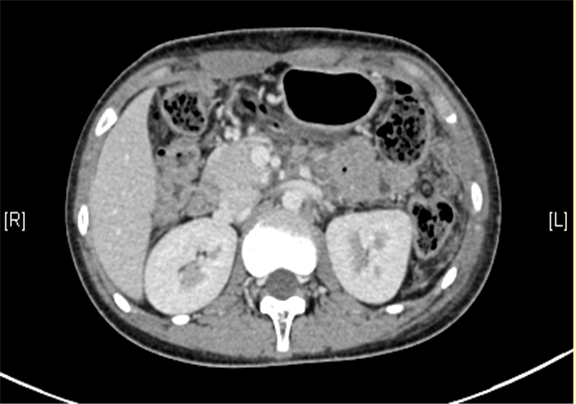

上腹部三维CT动态增强扫描: 胰腺体尾部类圆形软组织肿块,考虑实性假乳头状瘤可能性大。

术前CT检查:

平衡期